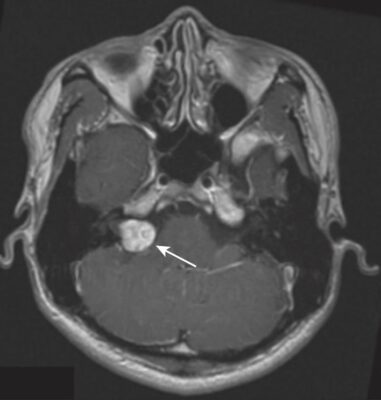

U tế bào Schwann (Schwannoma) tiền đình (U dây thần kinh thính giác, Acoustic Neuroma)

- Schwannoma tiền đình là những u tế bào Schwann thường gặp nhất trong tất cả các dây thần kinh sọ. Triệu chứng phổ biến nhất là giảm thính lực, nhưng cũng có thể có ù tai và rối loạn thăng bằng.

- U này thường ở dọc theo đường đi của dây thần kinh số VIII trong ống tai trong ở góc tiểu não – cầu não (Hình 30).

- Tương tự như u màng não, khi có nhiều khối u (tức là ở hai bên), chúng thường liên quan đến u xơ thần kinh loại 2.

- MRI có tăng cường chất đối quang từ là nghiên cứu hình ảnh nhạy nhất để phát hiện u tế bào Schwann tiền đình, hầu như luôn tăng cường tín hiệu, thường là đồng nhất. Trên hình ảnh T2W lát cắt mỏng, có thể thấy u bên trong ống tai trong.